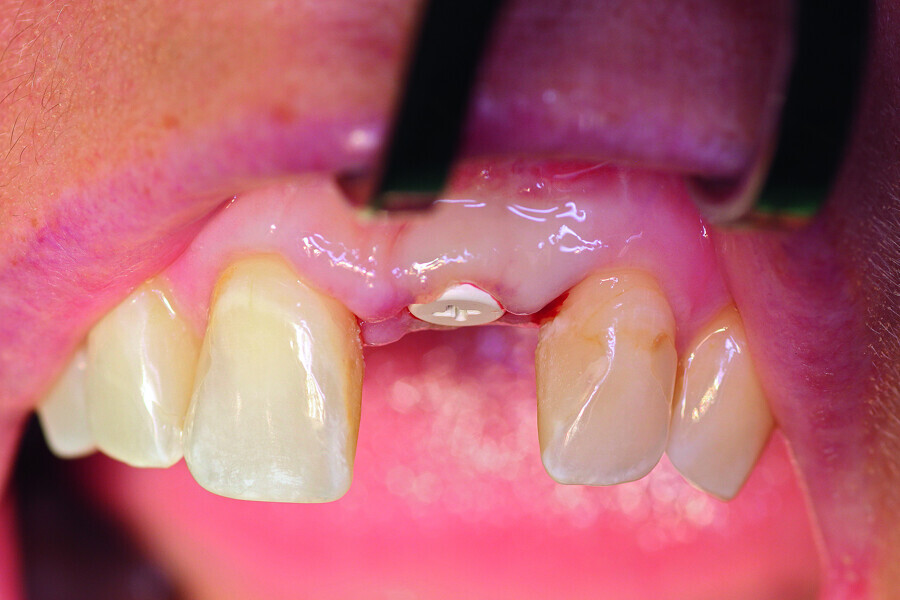

Fig. 7: Implant exposure after another four months.

Fig. 8a: A PEEK abutment as the base for the long-term temporary restoration.

Fig. 8b: A PEEK abutment as the base for the long-term temporary restoration.